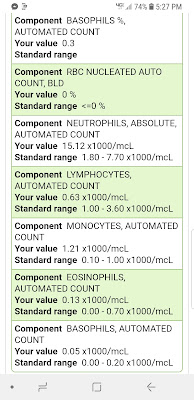

I just can't believe that 9 years ago this time Myeloma was RAGING inside of me, and I didn't know it yet.... My IGA was close to 5800 (normal = 70-400). My M Protein was over 4.3 (normal = 0) and my first Bone Marrow Biopsy showed 70% cancerous myeloma plasma cells! And here I am to talk about it, almost 9 years later, having survived more rounds chemo than I can count, a Stem Cell Transplant, and all the 9 years of side effects I have endured! But I'll reminisce about all of this soon...

1- Yes I bit the dust and got sick, but thankfully only a lousy head cold. Seriously, how amazing is that! I go on a Cruise with 2000-3000+ humans, and only get a lousy head cold! Guess those magical Zarxio, Neupogen WBC immune system building injections gave me some back up power to fight off all the potential nasty cooties out to get me! I am very cautious and careful though, and incessantly wash and sanitize my hands, myself, those around me, my living space, etc. I tried very hard to not let anyone touch me, hug me, and I never shake hands, I use antibacterial wipes to touch most anything public, and I brought my Mint Isopropyl Alcohol spray to sanitize and spray anything and everything and everyone! My finger nails even turned a lovely light green from the the Wintergreen color LOL. Wow, I sound like a freak... but it worked... I did not get any deadly viruses, bacterial yuckies or pneumonia, etc...

I'm also armed with Zofran, but I don't think I'll "pregrame" with that just yet, as I'll be on the high dose, 40mg Dex steroids, and that should help with any nausea, right?? Suggestions please!!!, if you've done this combo, which most of the Myeloma patients have, early on! Why didn't I?? I was concerned about all the warnings from myeloma patients about BAD Neuropathy from Velcade, so I skipped over to Kyprolis, and never had the Cytoxan pills added in, as Kyprolis Dex worked for me for about 10 months, then Darzalex, Pomalyst, Dex worked for me for about 18 months, so here I am, going backwards to meds I skipped, before I'll do clinical trials, CAR T, etc. Yes, no matter how "bad" my situation becomes, Quality of Life is first and foremost to me... since what's the point of treating myeloma, if I'm so sick all the time, I'm not living. Isn't the point of treatment to give a cancer patient their life back??? I've been doing this for almost 9 years now, and for so many hours, days, weeks, months, etc, my life has been so limited by side effects, I learned that for me, the treatment has to make sense... kill the cancer cells, but let me see the sunshine too!